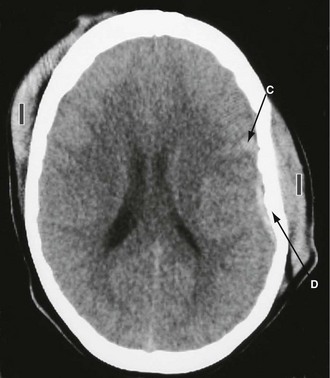

Subdural haematoma: Subdural haematoma usually results from tearing of veins passing between cerebral cortex and dura, or from injury to vessels on the surface of the brain. Blood accumulates in the large potential space between dura mater and arachnoid mater. The haematoma tends to spread laterally over a wide area (Fig. 16.6). In contrast to extradural haemorrhage, there is usually underlying primary brain injury. Acute subdural haemorrhage is more common in older adults because the brain is more mobile within the cranial cavity.

In an acute subdural haemorrhage, there is usually clinical evidence of brain injury at the outset. A lucid interval between initial loss of consciousness and later deterioration is rare, except where the pathology is tearing of a bridging vein. Evacuation of an acute subdural haematoma cannot be achieved via burr holes because the blood is clotted. Surgical evacuation via craniotomy may halt deterioration but recovery is often incomplete because of the underlying brain injury. With increasing use of anticoagulation and antiplatelet therapy, acute subdural haematoma is seen more commonly after relatively inconsequential injury, particularly in the elderly.